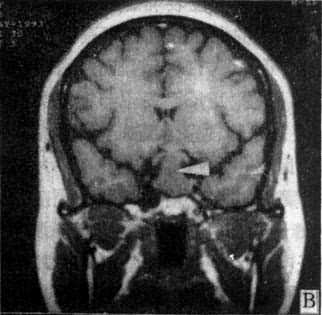

MRI因无骨骼伪影干扰,且有多维扫描断面和多种参数成像的优点,适宜于鞍区(图5-1-6A、B)和颅底特别是后颅凹病变的观察;应用血管的流空效应不用造影剂即可显示肿瘤与周围血和宾关系和供血情况。Gd-DTPA的应用可早期发现微小听神经瘤、垂体微腺瘤以及肿瘤的脑膜侵犯。MRI对钙化病变的显示不如CT敏感。

图5-1-6 MRI扫描SE序列图像

在矢状面(A)和冠状面(B)T1WI可见垂体肿块向鞍上延伸,呈等信号区(→);在横断面T1WI(C)和T2WI(D)上分别可见左枕和右基底节区脑梗塞灶呈低和高信号区(→);在矢状面T1WI(E)和横断面T2WI(F)上,可见基底动脉瘤环形影,其内为低信号和高信号区,高信号区为瘤内血栓形成(→)